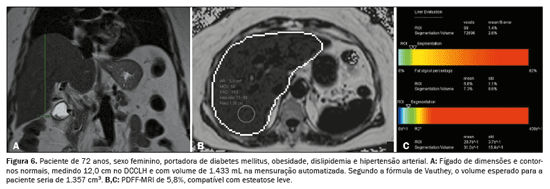

A associação, tanto do DCCLH e a PDFF-MRI (rs = 0,474;

p < 0,001) quanto da Voe e a PDFF-MRI (rs = 0,568;

p < 0,001), apresentou correlação estatisticamente significante, refletindo os resultados das análises anteriores (Figura 5). A relação entre o acúmulo de gordura e o aumento do volume hepático está exemplificada nas Figuras 6, 7 e 8.